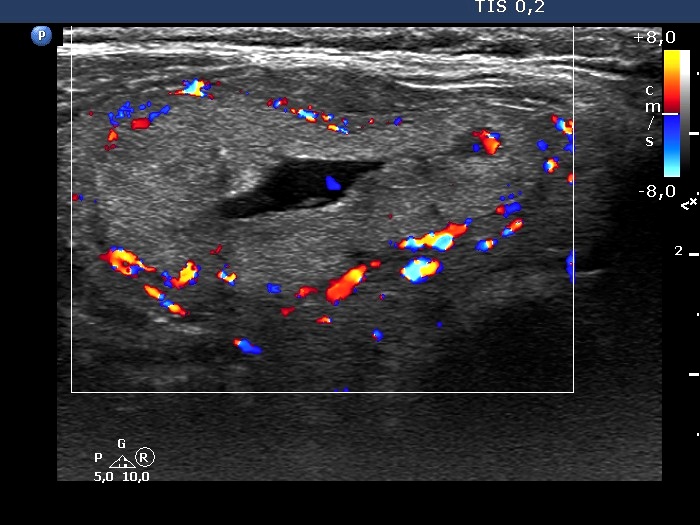

Right lobe, longitudinal scan

Right lobe, transverse scan, color Doppler mode - after aspirating 4 mL serous fluid. The vascularization has not changed.